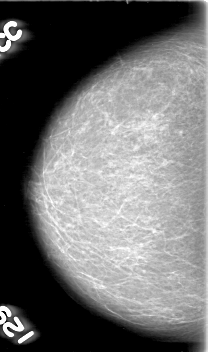

D_4055_1.RIGHT_MLO

D_4055_1.RIGHT_CC

RIGHT_CC LINES 5266 PIXELS_PER_LINE 3106 BITS_PER_PIXEL 12 RESOLUTION 43.5 NON_OVERLAY

RIGHT_MLO LINES 5311 PIXELS_PER_LINE 3271 BITS_PER_PIXEL 12 RESOLUTION 43.5 NON_OVERLAY